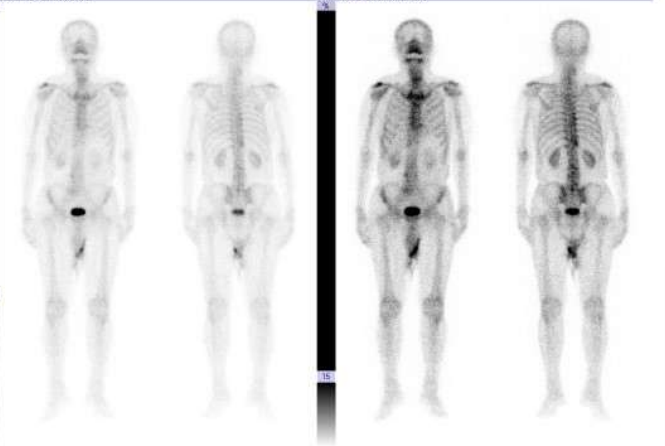

全身骨显像:第7、8、11胸椎及第3腰椎骨质代谢异常,建议进一步检查除外肿瘤骨转移可能。

图2 2024年12月3日ECT检查